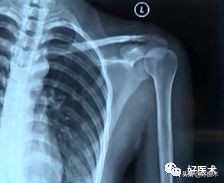

- X线照片:左侧:术前;右侧:术后

- X线照片:左侧:健侧;右侧:患侧术后